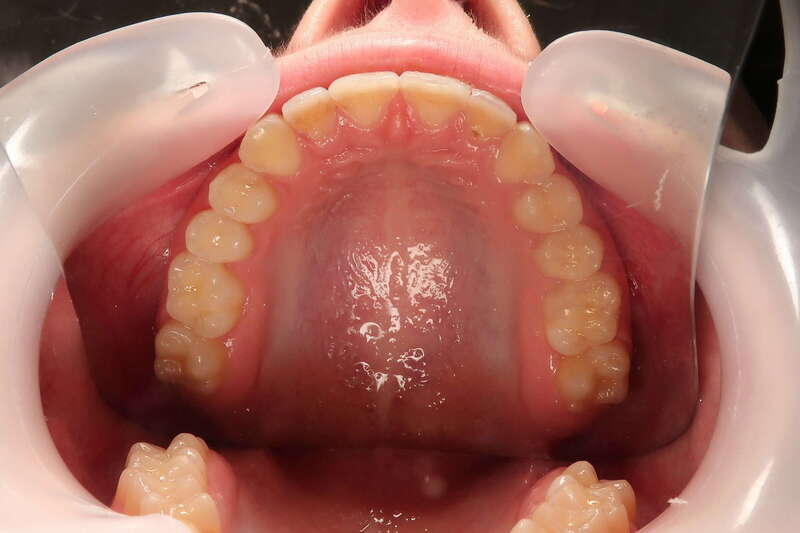

Cas n°9 traité par multi-attaches - adolescent

Ce cas d'adolescent illustre une stratégie de développement d'arcade réussie. Le patient présentait un encombrement massif et des inversions d'articulé rendant l'occlusion instable.

Le traitement a été réalisé avec des multibagues autoligaturantes, choisies pour leur capacité à générer des forces légères et continues, idéales pour l'expansion transversale. Cette approche a permis de corriger l'encombrement et les inversions d'articulé sans extractions dentaires, en remodelant simplement la forme des arcades.

Résultats clés :

• Transformation d'arcade : Passage d'une arcade étroite et encombrée à une arcade large et fonctionnelle.

• Occlusion optimale : Rétablissement d'un engrènement sain, protégeant les dents contre les usures anormales.

• Esthétique naturelle : Le sourire est élargi, harmonieux et parfaitement intégré au profil du patient.

C'est une démonstration de l'efficacité biologique de l'orthodontie moderne, qui privilégie la conservation dentaire et le respect des structures osseuses.

Avant le traitement

Pendant le traitement

Après le traitement